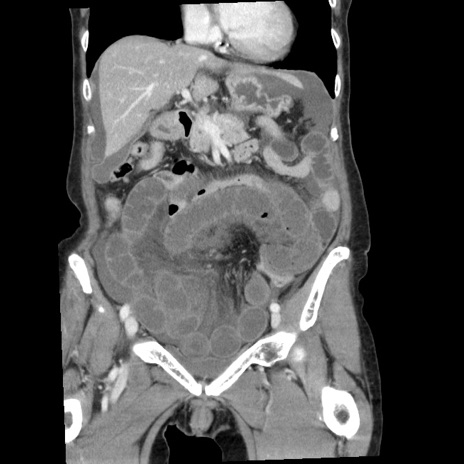

症例1(冠状断像)

【症例】80歳代女性

【主訴】腹痛

【現病歴】8時間前から腹痛あり来院。

【既往歴】糖尿病、脂質異常症、子宮体癌にて子宮全摘術

【身体所見】意識清明・会話良好だが腹痛で苦悶様、全腹部にわたって反跳痛と圧痛あり

【データ】WBC 13600、CRP 0.14、LDH 224、CK 90